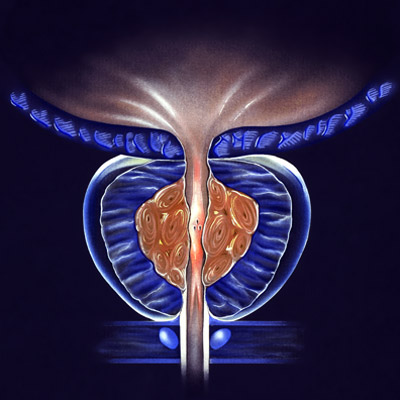

TECHNOLOGIE DE DERNIÈRE GÉNÉRATION

Nos professionnels croient en les équipements de pointe qui permettent des procédures d’intervention mini-invasives, ainsi que des procédures chirurgicales très complexes.

Robot chirurgical "DA VINCI XI"

PROFESSIONNELS

Le savoir et l’expérience acquis durant plus de 100 ans et s’accompagnant d’une vision exhaustive ont permis à nos professionnels de se placer dans une position de leadership et de référence en ce qui concerne les pathologies les plus complexes.